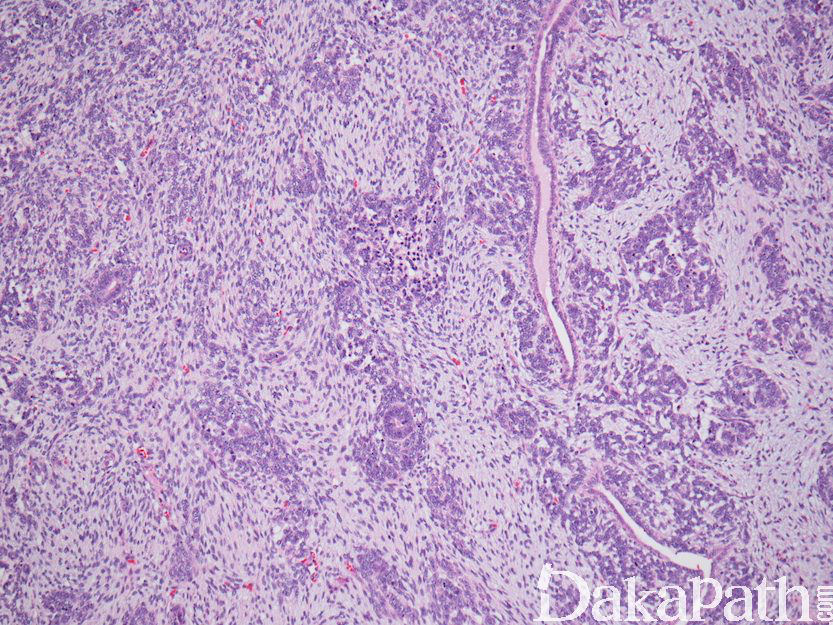

- 肾源性残余可临近与肾母细胞瘤或位于周围肾实质中。形态学上肾源性残余由致密成巢和弥漫成片的原始胚芽、小管以及数量不等的间质组成,无软骨和原始间充质成分,通常无瘤细胞的间变。组织学上肾源性残余可分为为叶周型和叶内型,其结构上差别见下表,肾源性残余在组织学上可再分为:静止型,成熟型/硬化型/废弃型,增生性,肿瘤性等。

- 叶周型肾源性残余

a)边界清楚,位于肾叶周缘(肾皮质表面,髓质柱中央,肾窦边缘等),可静止存在,也可有其他的转归;多数退化形成废弃残余,即肾小管周围的瘢痕,也可过度生长形成增生的肾源性残余,此时,几乎不可能与肾母细胞瘤相鉴别;

c)伴发肾母细胞瘤者呈半球形膨胀性生长,肾母细胞瘤成分周围有纤维性包膜使之与叶周型肾源性残余和正常肾组织分隔; - 叶内型肾源性残余

- 主要位于肾叶中央区,边界不清,由间叶组织和上皮性小管构成,其转归也可呈静止状态、退化和增生;

- 肾母细胞瘤伴叶内型肾源性残余者,有纤维性假包膜将肾母细胞瘤与肾源性残余分隔。